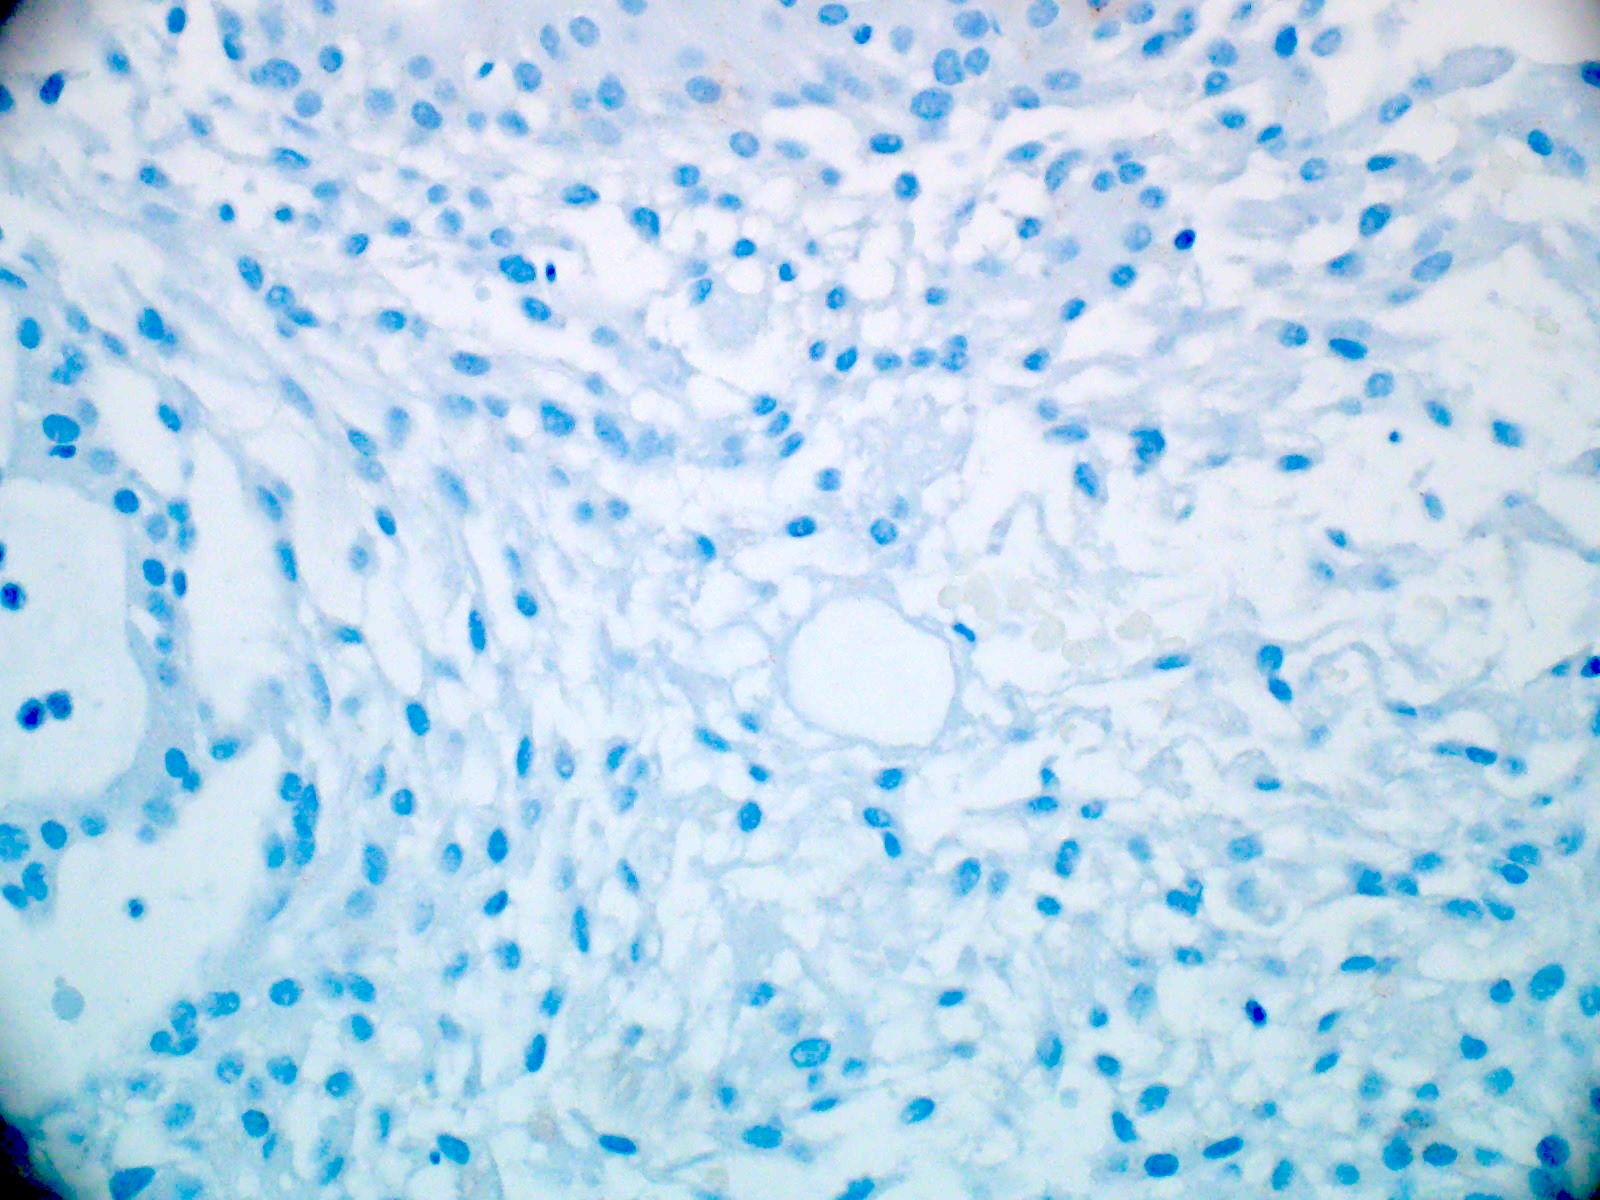

Microscopic (histologic) description

- Most common pattern is radial arrangement of cuboidal to epithelioid elongated glial tumor cells around hyalinized fibrovascular (central, often hyalinized blood vessels) cores in a papillary configuration

- Accumulation of basophilic myxoid material around blood vessels (myxoid stroma) and in microcysts

- Myxoid material is highlighted by PAS and Alcian blue positive staining

- In cases composed of confluent sheets of epithelioid cells with little or no papillary structures, PAS and Alcian blue positivity is useful in reaching a correct diagnosis

- Fascicular growth and spindle cells are common

- Pleomorphic tumor giant cells can be seen

- Occasionally tumor cells show distinctive eosinophilic balloons; these are PAS positive spherules that demonstrate spiculated reticulin staining (Am J Surg Pathol 1996;20:1091)

- Uncommon examples reported as anaplastic myxopapillary ependymomas show hypercellularity and reduced mucin in association with at least 2 of the following features: ≥ 5 mitoses / 10 high power field, Ki67 labeling index ≥ 10%, microvascular proliferation, spontaneous necrosis (Brain Pathol 2019;29:75)

Microscopic (histologic) images